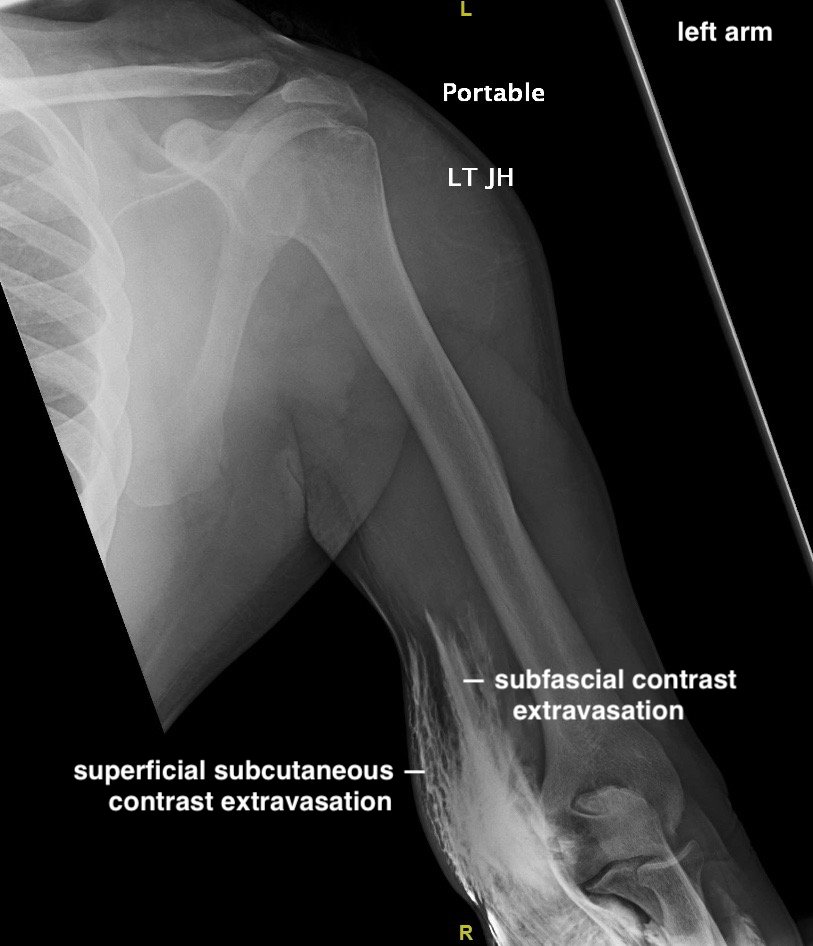

Asymptomatic CT Iodinated Contrast Extravasation of the Upper Extremity

A 39-year-old male with a history of type 2 diabetes was brought in by ambulance to the emergency department as a trauma status post motor vehicle versus pedestrian accident. The patient was walking along a surface street when he was struck on the left side of his body by a vehicle traveling approximately 35 miles per hour. On arrival, he complained of generalized left-sided body pain. An 18-gauge intravenous (IV) line was placed in the left antecubital fossa and a computed tomography (CT) of the chest, abdomen and pelvis was obtained with iodinated contrast. Shortly after acquiring CT images, portable radiographs were taken of the upper and lower extremities revealing iodinated contrast extravasation into the left distal arm, left antecubital fossa and left proximal forearm. Other than mild left-sided shoulder pain, the remainder of the patient’s left upper extremity was asymptomatic. The patient had an unremarkable neurovascular exam and upper extremity compartments were soft. Throughout the patient’s ED course, there were no further signs or symptoms of compartment syndrome (ie,the classic 5 P’s of pain, paresthesias, pallor, paralysis, and pulselessness).

The two radiographs demonstrate extravasation of radiopaque iodinated contrast in the lower left upper extremity with most seen in the left antecubital fossa and left proximal forearm. Extravasation is seen in the subcutaneous and subfascial tissue.